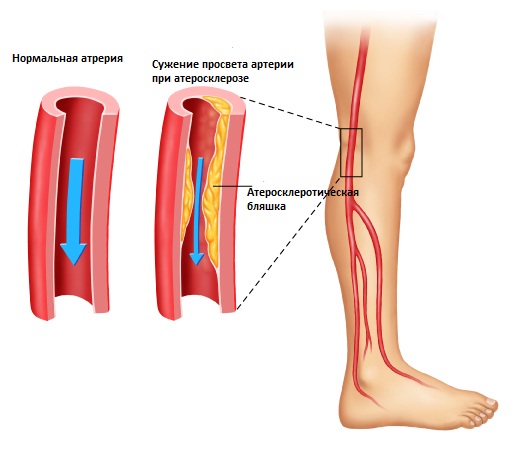

К врожденным причинам относится недоразвитие аорты и формирование фиброзно-мышечной дисплазии в период внутриутробного развития. Приобретенные состояния, возникающие с возрастом, включают атеросклероз артерий, постэмболитический тромбоз и аортоартериит. Наиболее распространенной причиной окклюзии является атеросклероз.

Развитие заболевания зависит от степени поражения аорты и ее подвздошных ветвей. Со временем нижние конечности и внутренние органы, находящиеся в области таза, начинают получать все меньше крови, кислорода и питательных веществ. Участки выше сужения перегружаются, а в нижних конечностях постепенно развивается кислородное голодание, известное как ишемия.

Атеросклеротическая бляшка.

Наиболее заметные изменения, связанные с атеросклерозом, проявляются в области деления аорты и в местах ответвления подвздошной артерии.

- На внутренних стенках сосудов образуются отложения кальция (кальциноз). Кальцинаты состоят из мертвых тканей, погибших в результате инфекции или травмы. Кальциноз приводит к хрупкости сосудов, что увеличивает риск их разрыва при повышении давления и напряжении. Удалить кальцинаты из организма невозможно.

- Еще одно явление, связанное с атеросклерозом, — это пристеночный тромбоз. При наличии неспецифического аортоартериита больше всего страдает аорта. Ее стенки подвергаются кальцинозу, а участки воспаления утолщаются.